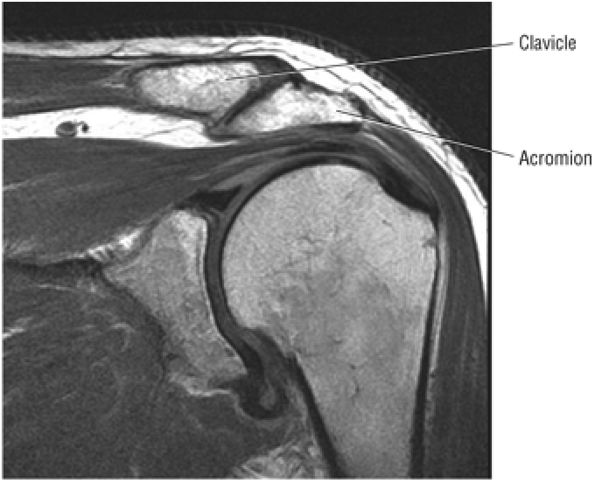

The coracoclavicular ligaments are also displayed on anterior coronal oblique images. The anatomy of the AC articulation is best displayed at the level of the supraspinatus tendon. When present, AC joint fluid may represent an asymptomatic manifestation of osteoarthritis.41

Medial sagittal sections display the clavicle and AC joint in profile. The oblique transversely oriented physis is also delineated on sagittal images. Marrow inhomogeneity, seen frequently as red-to-yellow marrow conversion, may not be complete distal to the physis in the metadiaphyseal region.43

The clavicle connects the axial and appendicular skeletons of the upper extremity.44 It is S-shaped in configuration, with a convex anterior border medially and a concave

P.1195P.1196

anterior border laterally. It is flattened and narrowed laterally and has a thicker cylindrical configuration medially. The clavicle articulates with the sternoclavicular joint medially and with the AC joint laterally (Fig. 8.57). The surfaces of the sternoclavicular joint are covered by fibrocartilage, and a fibrocartilaginous articular disk divides the joint into separate recesses.45 -